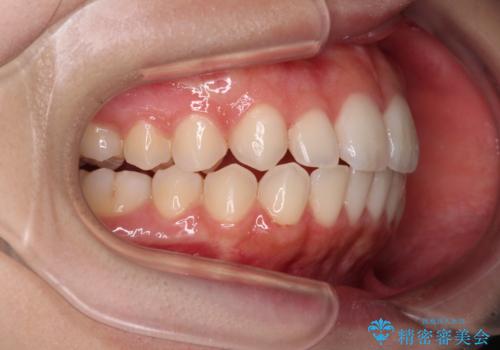

【モニター】前歯のクロスバイトをインビザラインで治療

- 前歯のデコボコとクロスバイトを気にして来院された患者様です。

上顎側切歯(上の真ん中から2番目の歯)が舌側転位している場合、インビザラインでは仕上げきれないことが多く、更には無理して動かそうとすると歯髄壊死を起こすリスクが高いと言われています。

今回は、ワイヤー装置を併用することなく、インビザライン単体で矯正治療を行うこととしました。

インビザライン特有の、奥歯の咬み合わせの問題もなく、しっかりと歯列を改善することができました。

舌側転位している上顎側切歯(内側に引っ込んでいる真ん中から2番目の歯)は、インビザラインが最も移動を苦手とする歯であり、これ以上の改善を望まれる場合にはワイヤー矯正、あるいはワイヤー矯正の併用をお勧めいたします。